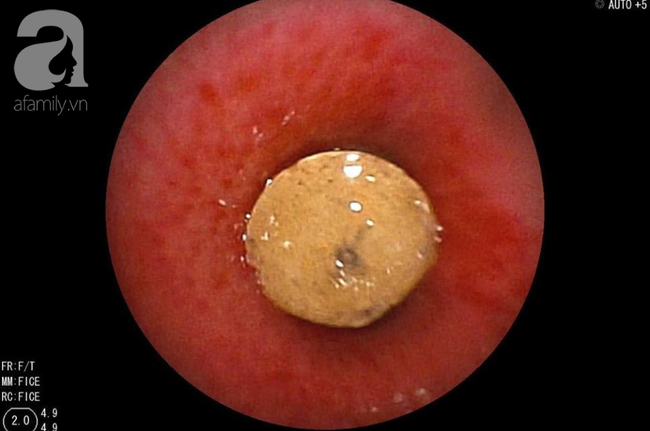

Các BS quyết định phải soi phế quản khẩn cấp. Kết quả là ekip phát hiện một mẩu nhựa cứng khô mà trước đó các BS còn mường tượng là cục đá.

Dị vật được lấy ra hết sức cẩn thận và cũng đầy thử thách vì nằm sâu trong phởi và trơn trợt, lại kẹt bít lòng phế quản đã phù nề, viêm trợt do bị chèn ép.

Dị vật qua nội soi.